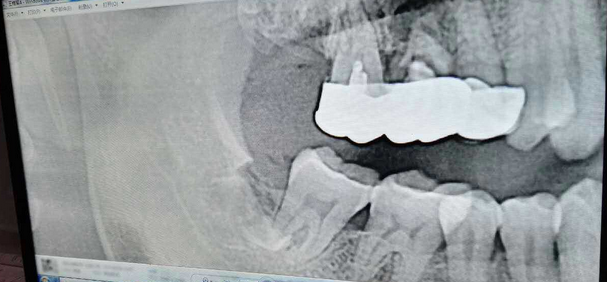

超聲牙周刮治案例

病例:患者男性47歲

右下8骨埋伏并且黏連;從根分叉處通過;有彈性;術中看到神經(jīng)束

實在找不到;近中牙冠沒去干凈

像這種不切除的牙冠,以后吸收的可能性不是很大,但有排除的可能性,自己自行排出,要是牙根的話吸收的可能性比較大

像這種沒有癥狀的殘留牙體組織不用去除可以吧